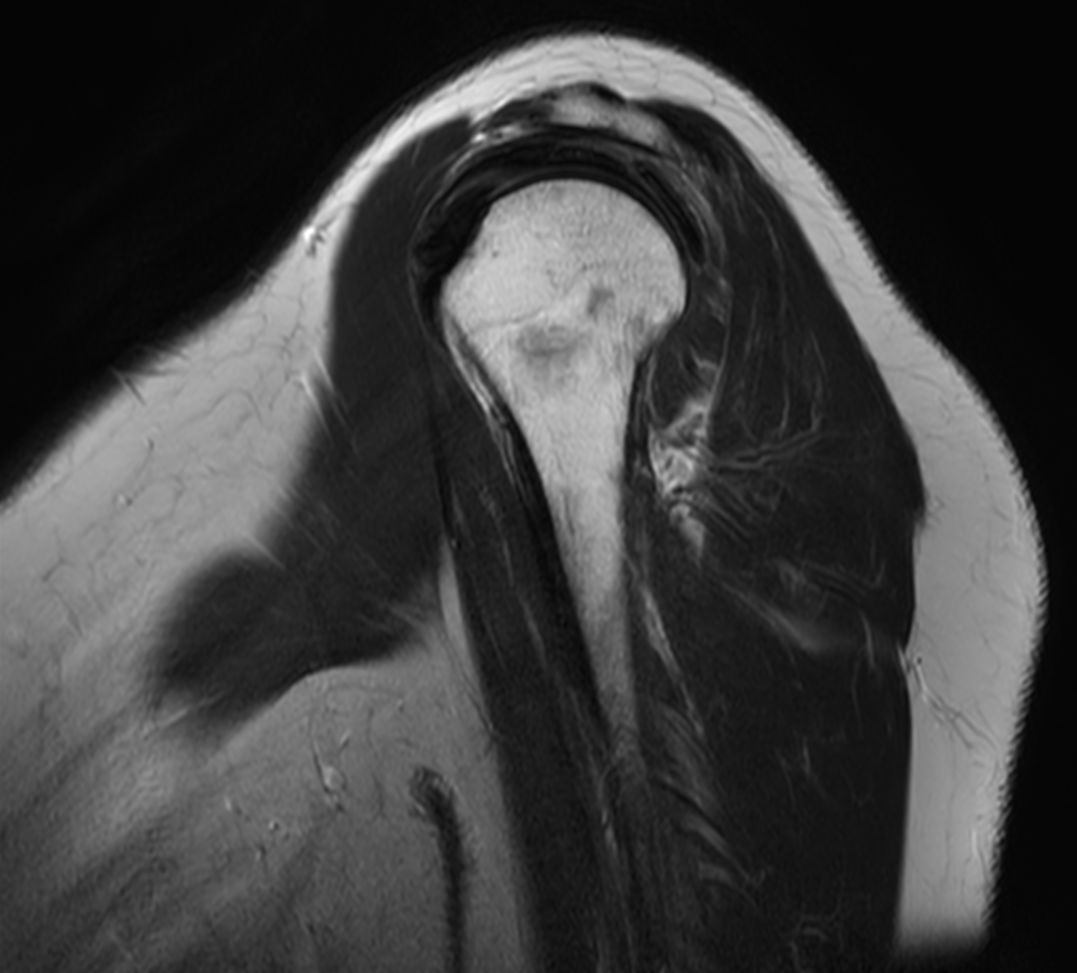

Coronal T2w SPAIR